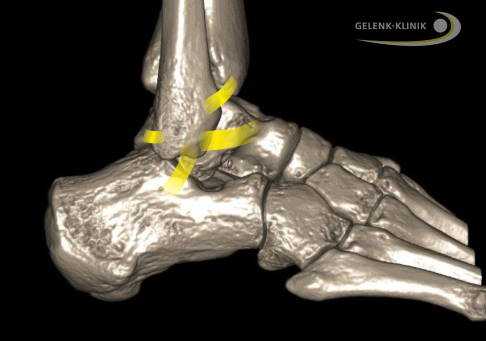

Внешние связки соединяют малоберцовую кость (Fibula) с пяточной и таранной костями. Межберцовый синдесмоз проходит между большеберцовой и малоберцовой костями. © Gelenk-Klinik

Реконструкция связок голеностопного сустава является операцией по лечению хронической нестабильности. Эта нестабильность приводит при малейших нагрузках к вывихам лодыжки. При этом наблюдается повышенная подвижность самого голеностопа, что является большей нагрузкой на суставный хрящ, что обычно, и приводит к его разрушению.

Причинами разрыва связок лодыжки зачастую являются падения либо травмы во время занятий спортом. Связки теряют свою стабилизирующую функцию, и пациенты больше не могут двигаться как раньше. Чаще всего повреждениям подвержены внешние связки. Передняя таранно-малоберцовая связка травмируется почти при всех повреждениях латеральных связок.